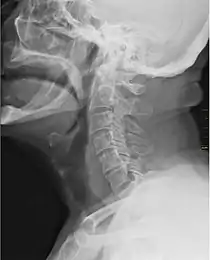

![]() X-ray showing the throat, seen as a dark band to the front of the spine. | |